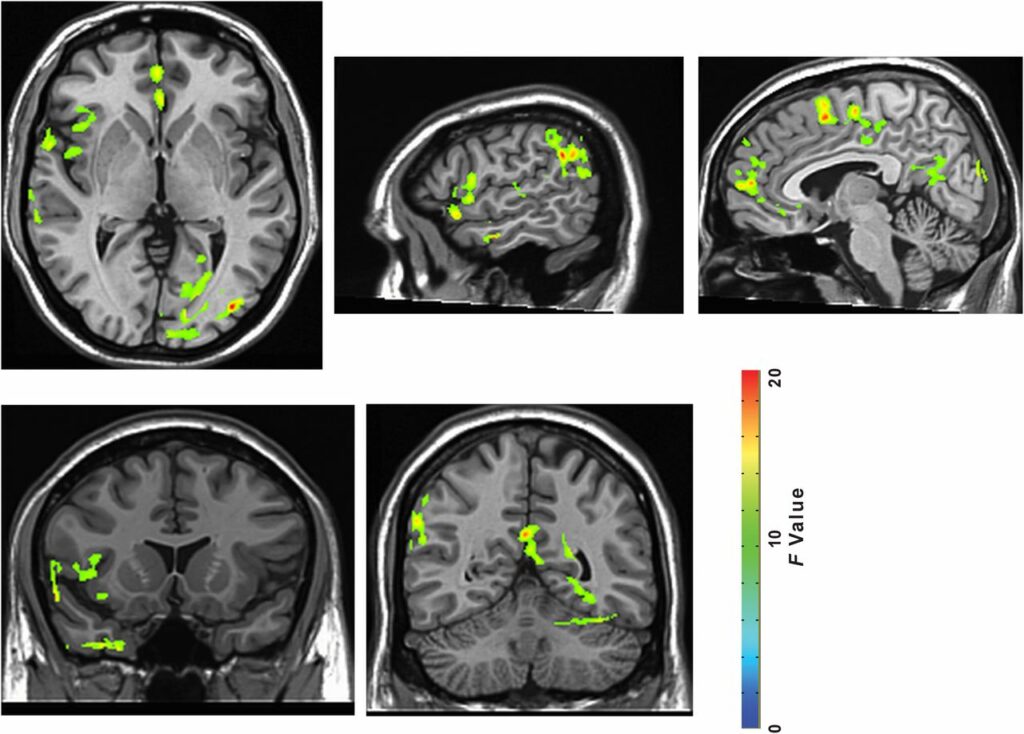

The impact of nature experience on self-reported rumination and blood perfusion to the sgPFC. (A) Change in self-reported rumination (postwalk minus prewalk) for participants randomly assigned to take a 90-min walk either in a natural setting or in an urban setting. (B) A time-by-environment interaction in blood perfusion was evident in the sgPFC. F map of significant interactions at a threshold of P < 0.05, FWE corrected for multiple comparisons. (C) Change in blood perfusion (postwalk minus prewalk) for participants randomly assigned to take a 90-min walk either in a natural setting or in an urban setting. Error bars represent SE within subjects: *P < 0.05, ***P < 0.001.

To analyze the impact of nature experience on blood perfusion in the sgPFC, we conducted a similarly structured ANOVA with time as a within-subjects factor (before vs. after the walk) and environment as a between-subjects factor (nature walk vs. urban walk). Clusters reflecting a significant time-by-environment interaction were corrected for familywise error (FWE; voxelwise P = 0.05, cluster threshold = 1,713 mm3) for multiple comparisons across the whole brain. The sgPFC was the a priori area of interest in this study (Table S1 and Fig. S3 for whole brain analyses). All reported perfusion values are in units of milliliters of blood per 100 g tissue per minute. As hypothesized, sgPFC perfusion showed an interaction effect of time by environment, indicating an effect of the nature walk vs. the urban walk [Fig. 1B; F(1,29) = 23.41, P < 0.0001, η2pηp2 = 0.45].

Fig. S3.

All brain regions showing time-by-environment interaction (P < 0.05, FWE corrected). Slice coordinates from left to right: z = 1, x = 55, x = 5, y = 13, y = −52.

We investigated the composition of this interaction in the sgPFC by examining (for each participant and scan) cerebral blood flow estimates centered at the cluster peak. As predicted, follow-up t tests revealed that our results were driven by decreases in blood flow resulting from nature vs. urban experience. There was an effect of time for the nature group [t(15) = −6.89, P < 0.0001, d = 1.01] with decreases from pre- to postwalk in the nature group, but there was no effect of time for the urban group (Fig. 1C).